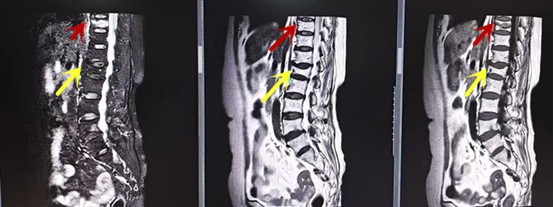

利器三:MRI(核磁共振)

MRI利于磁場和射頻脈沖使體內(nèi)的氫原子核發(fā)生磁共振現(xiàn)象而產(chǎn)生的圖像,對軟組織的分辨率很高,對于脊髓、椎間盤、神經(jīng)、血管、韌帶、骨髓、腰部肌肉及周圍軟組織有很好的顯示效果,可以清晰的顯示腰椎間盤突出對硬膜囊、神經(jīng)根壓迫程度,以及骨折是陳舊還是新鮮,同時在脊髓病變(如脊髓損傷、髓內(nèi)出血或腫瘤)、椎管內(nèi)膿腫/血腫、椎旁肌肉軟組織病變等方面也具有優(yōu)勢,但是檢查時間較長,部分患者可能因體內(nèi)金屬植入物(如心臟起搏器、人工耳蝸等)而無法進行檢查。

箭頭提示腰椎管內(nèi)腫瘤

紅色箭頭提示新鮮骨折,黃色箭頭提示陳舊性骨折